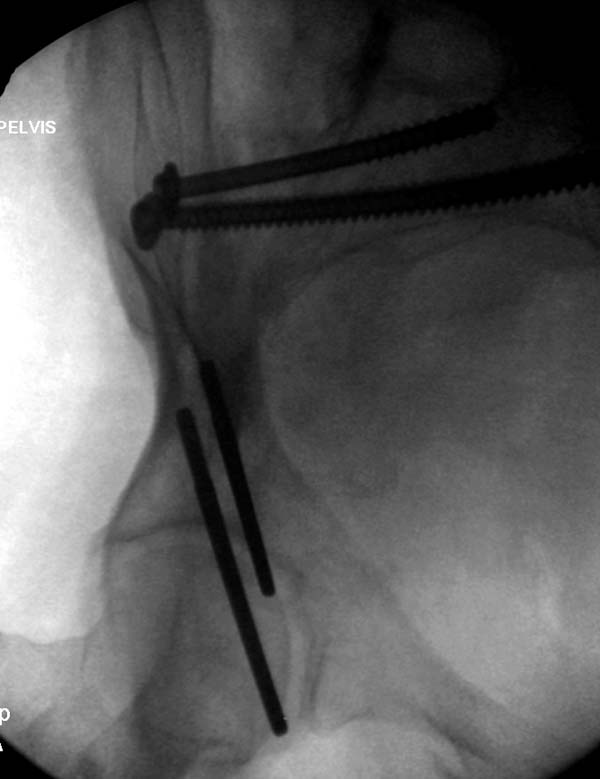

Большое спасибо всем Вам за помощь! Вчера прооперировали пациентку. Выполнили закрытую репозицию левой половины таза на тракционном столе под контролем ЭОП, закрытая фиксация левого КПС двумя каннулированными винтами. Учитывая удовлетворительное стояние отломков лонной и седалищной костей справа, а так же удовлетворительную ширину лона передние отделы стабилизировали системой ЦИТО

Послеоперационные КТ прилагаются

Винты введены в S1

Вроде бы все удалось. хорошо, что фрагмент (как выяснилось из КТ оказался небольшим), но для оценки лучше выкладывать рентген в стандартных проекциях